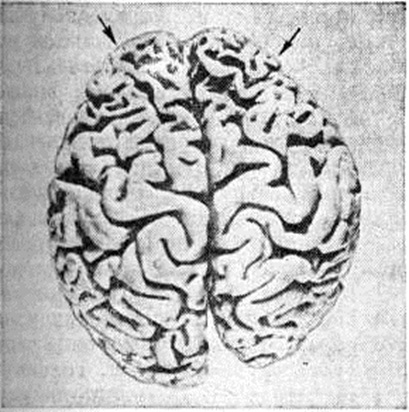

Патологическая анатомия. Патологоанатомические изменения при Пика болезнь характеризуются избирательной атрофией главным образом коры и белого вещества полушарий головного мозга. Иногда атрофия в значительно меньшей степени захватывает подкорковые узлы и стволовые отделы. Различают атрофию преимущественно лобных (рисунок 1) или височных долей, нередко — комбинированное их поражение. Часто в процесс вовлекаются теменные доли, однако изолированное их поражение, так же как и атрофия затылочных долей, встречается крайне редко. При атрофии лобных долей прецентральные извилины обычно остаются сохранными. Атрофия развивается, как правило, в симметричных участках обоих полушарий, иногда с большей выраженностью в левом и крайне редко — в правом полушарии.

Рис. 1.

Макропрепарат головного мозга при болезни Пика: выраженная атрофия извилин коры лобных долей (указано стрелками) и уменьшение размеров правого полушария головного мозга.